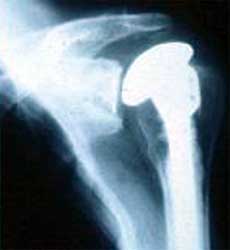

假体过大,假体位置肱骨近段截骨不足,肱骨头过高,引起疼痛活动受限。

翻修手术后,肱骨近段进一步截骨,更换小号肱骨头,矫正肱骨头过高